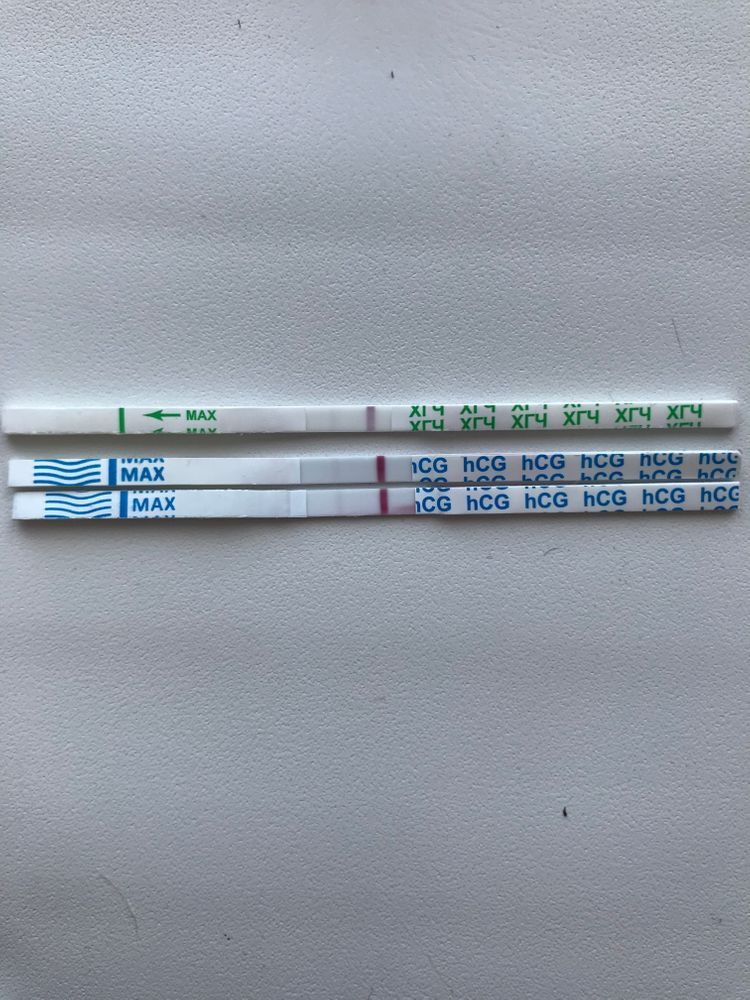

Был укол хгч 25000 МЕ, позовчера сдавала кровь, результат 5,7, ну понятно что хвост. Вчера тесты уже были пустые, да и сегодня утром и днём. Да, у меня 12 д.у и 9-10д.п.о.Сейчас сделала и опять призрок, это все от укола что-ли?

Анютка Никулча, обязательно дождётесь,вот у меня на 3 дз.Сейчас 5 и он слабый только что сделала.Этот же тест